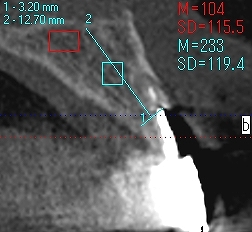

左上2,3番は虫歯も進行しており、抜歯してインプラントとなりました

インプラント埋入時になります

2番は3.25mmの13mmというインプラントを埋入しています

3番は4,0mmの13mmというインプラントを埋入しています